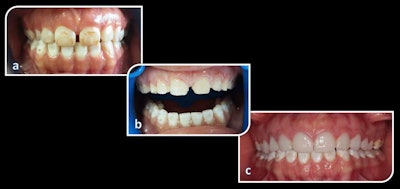

A patient with advanced fluorosis (a). The same patient during preparation for ceramic veneers (b). The patient after receiving veneers (c). All images courtesy of Demirekin et al. Licensed under CC BY 4.0.For about three decades, porcelain laminate veneers have been a good option for restoring anterior teeth due to biocompatibility, durability, and aesthetic appeal. Currently, veneers are reserved mostly to improve tooth form and position, hide tooth discoloration, and restore teeth with erosion or incisor wear. Veneers are a good alternative to crown restorations because they are minimally invasive, the authors noted.